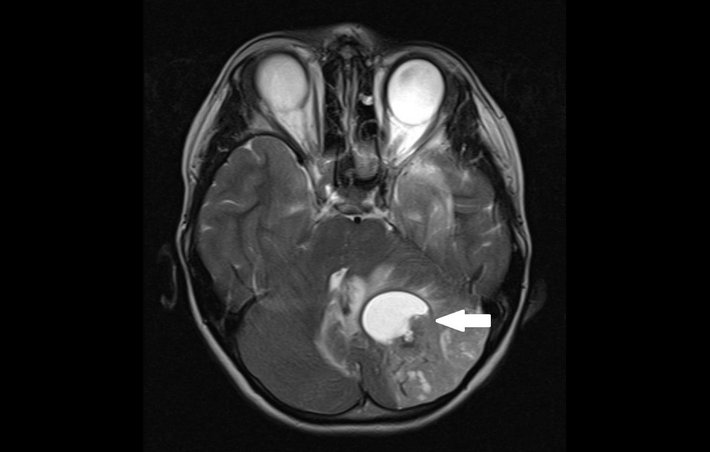

Dieser Hirntumor (dunkel) im Kleinhirn besitzt eine Flüssigkeitsblase (hell), die zusätzlich auf das Hirngewebe drückt.